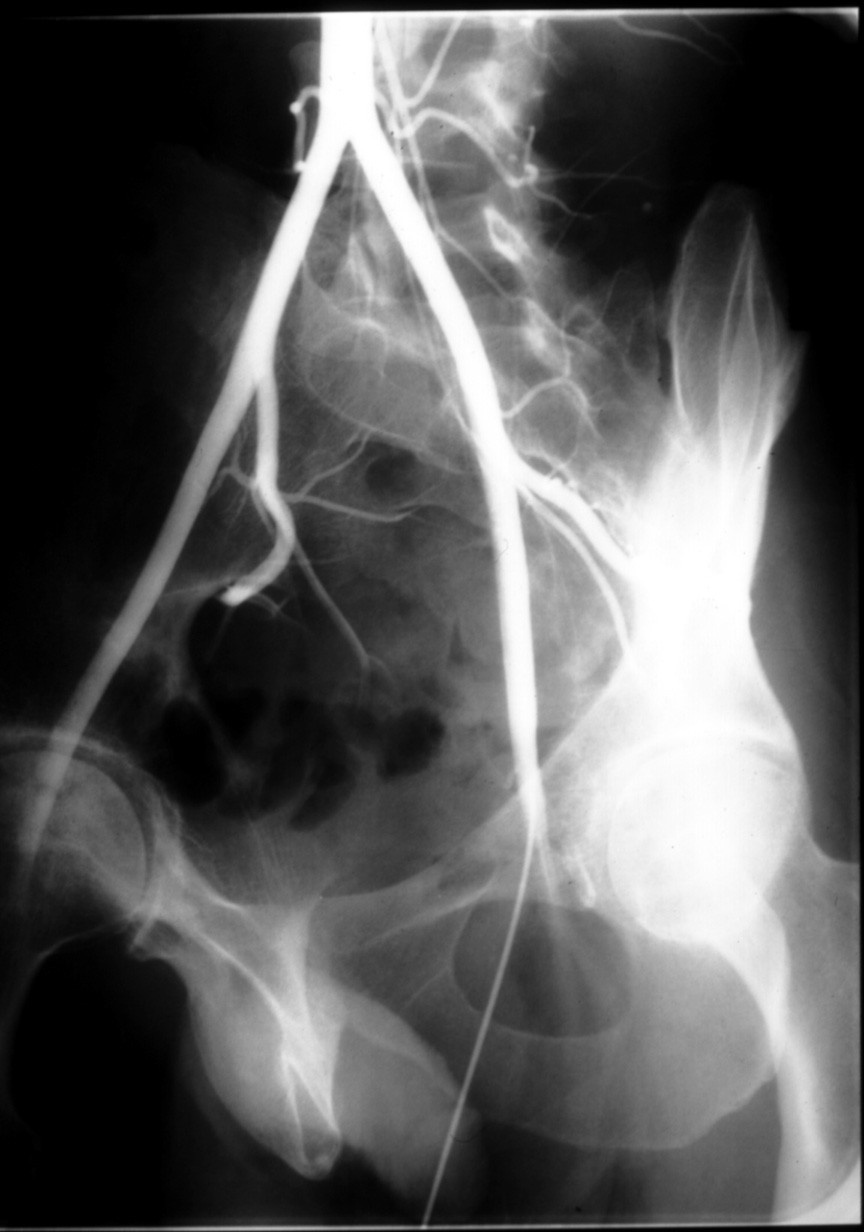

Identify:  abplpr31